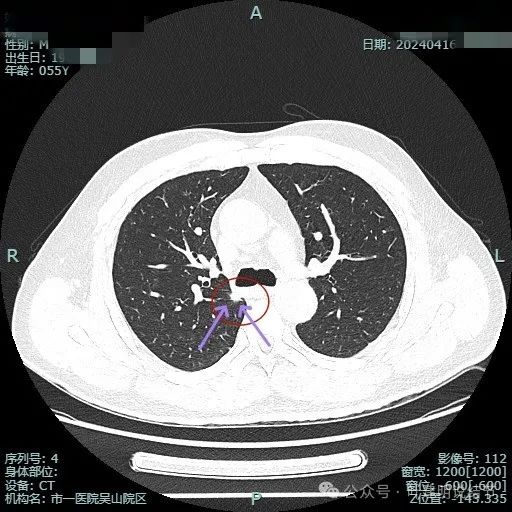

有明显血管征,而且进入的血管是弯曲改变走行的。

表面不平显毛糙,有细毛刺。

此层显得病灶缺乏膨胀性,边缘较为平直。